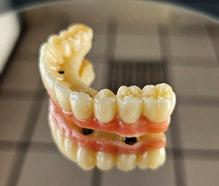

directamente a cabeza de implante para realizar una prótesis dentoalveolar de cerámica de 3 piezas, que equilibraran la oclusión y dieran soporte al labio y la mejilla (Figuras 14-17)

Figura 14. Imagen intraoral frontal postoperatoria al año de la reconstrucción.

Figura 15. Detalle de prótesis dentoalveolar cerámica en visión lateral.

Figura 16. Ortopantomografía postoperatoria.

Figura 17. Resultado final.